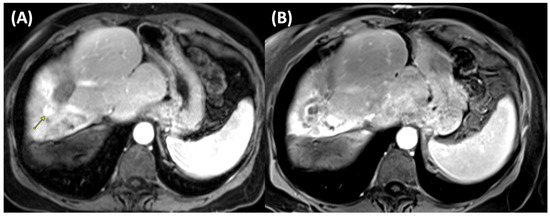

Case Report

Highlighting the Importance of Signaling Pathways and Immunohistochemistry Features in HCC: A Case Report and Literature Review

by Madalin Alexandru Hasan, Ioana Larisa Paul, Simona Cavalu, Ovidiu Laurean Pop, Lorena Paduraru, Ioan Magyar and Mihaela Doina Chirila

Reports 2025, 8(4), 197; https://doi.org/10.3390/reports8040197 - 3 Oct 2025

Background and Clinical Significance: In hepatocellular carcinoma (HCC), numerous signaling pathways become aberrantly regulated, resulting in sustained cellular proliferation and enhanced metastatic potential. Tumors that lack PYGO2 may not show the same types of tissue remodeling or regenerative features driven by the Wnt/β-catenin [...] Read more.

Background and Clinical Significance: In hepatocellular carcinoma (HCC), numerous signaling pathways become aberrantly regulated, resulting in sustained cellular proliferation and enhanced metastatic potential. Tumors that lack PYGO2 may not show the same types of tissue remodeling or regenerative features driven by the Wnt/β-catenin pathway, which could make the tumor behave differently from others that are Wnt-positive. PIK3CA-positive tumors are often associated with worse prognosis due to the aggressive nature of the PI3K/AKT pathway activation. This is linked to higher chances of metastasis, recurrence, and resistance to therapies that do not target this pathway. Case presentation: In this paper we present a rare case of hepatocellular carcinoma with PIK3CA-positive and PYGO2-negative signaling pathways, several key aspects of the tumor’s behavior, prognosis, and treatment options. Although alpha-fetoprotein (AFP) levels were significantly elevated, the CT and MRI examination showed characteristics of malignancy, HCC with secondary hepatic lesions and associated perfusion disturbances. The case particularities and immunohistochemistry features are highlighted in the context of literature review, the PIK3CA mutation suggesting the activation of the PI3K/AKT/mTOR pathway, a critical signaling pathway involved in cell survival, proliferation, and metabolism. Conclusions: Due to the aggressive nature of PIK3CA mutations, close monitoring and consideration of immunotherapy and targeted treatments are of crucial importance. Full article